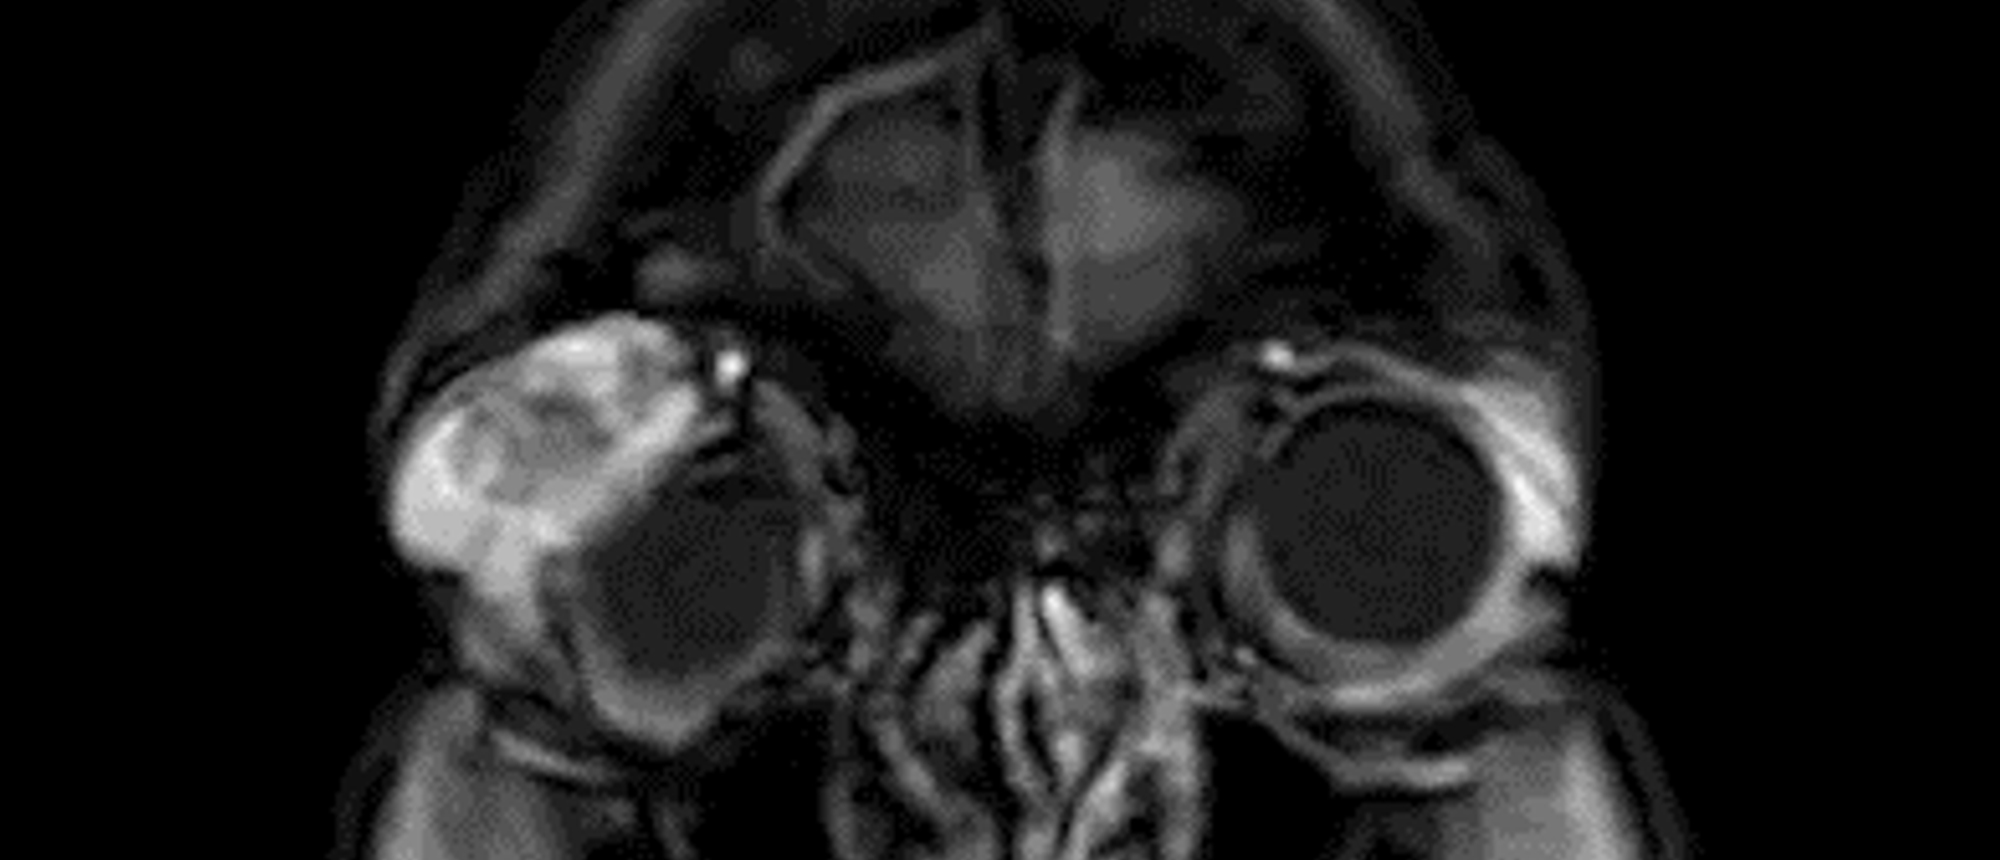

Melanocytoma with Vitreous Seeding

Specialty: Corneal and External Diseases

Include in Catalogue?: No

Presenter(s): Nathan L. Scott, MD, MPP

Faculty Discussant(s): Zelia M. Correa, MD, PhD; Sander R. Dubovy, MD

Melanocytoma with Vitreous Seeding A patient with 7 years of blurry vision in the right eye presents to clinic for evaluation. He reports no recent acute changes in vision and no precipitating events in the past. He noticed the blurry vision incidentally while driving when he covered his left eye. …

Specialty: Ocular Oncology

Type: Online Grand Rounds

Include in Catalogue?: Yes

Presenter/Faculty: Correa, Dubovy, Scott